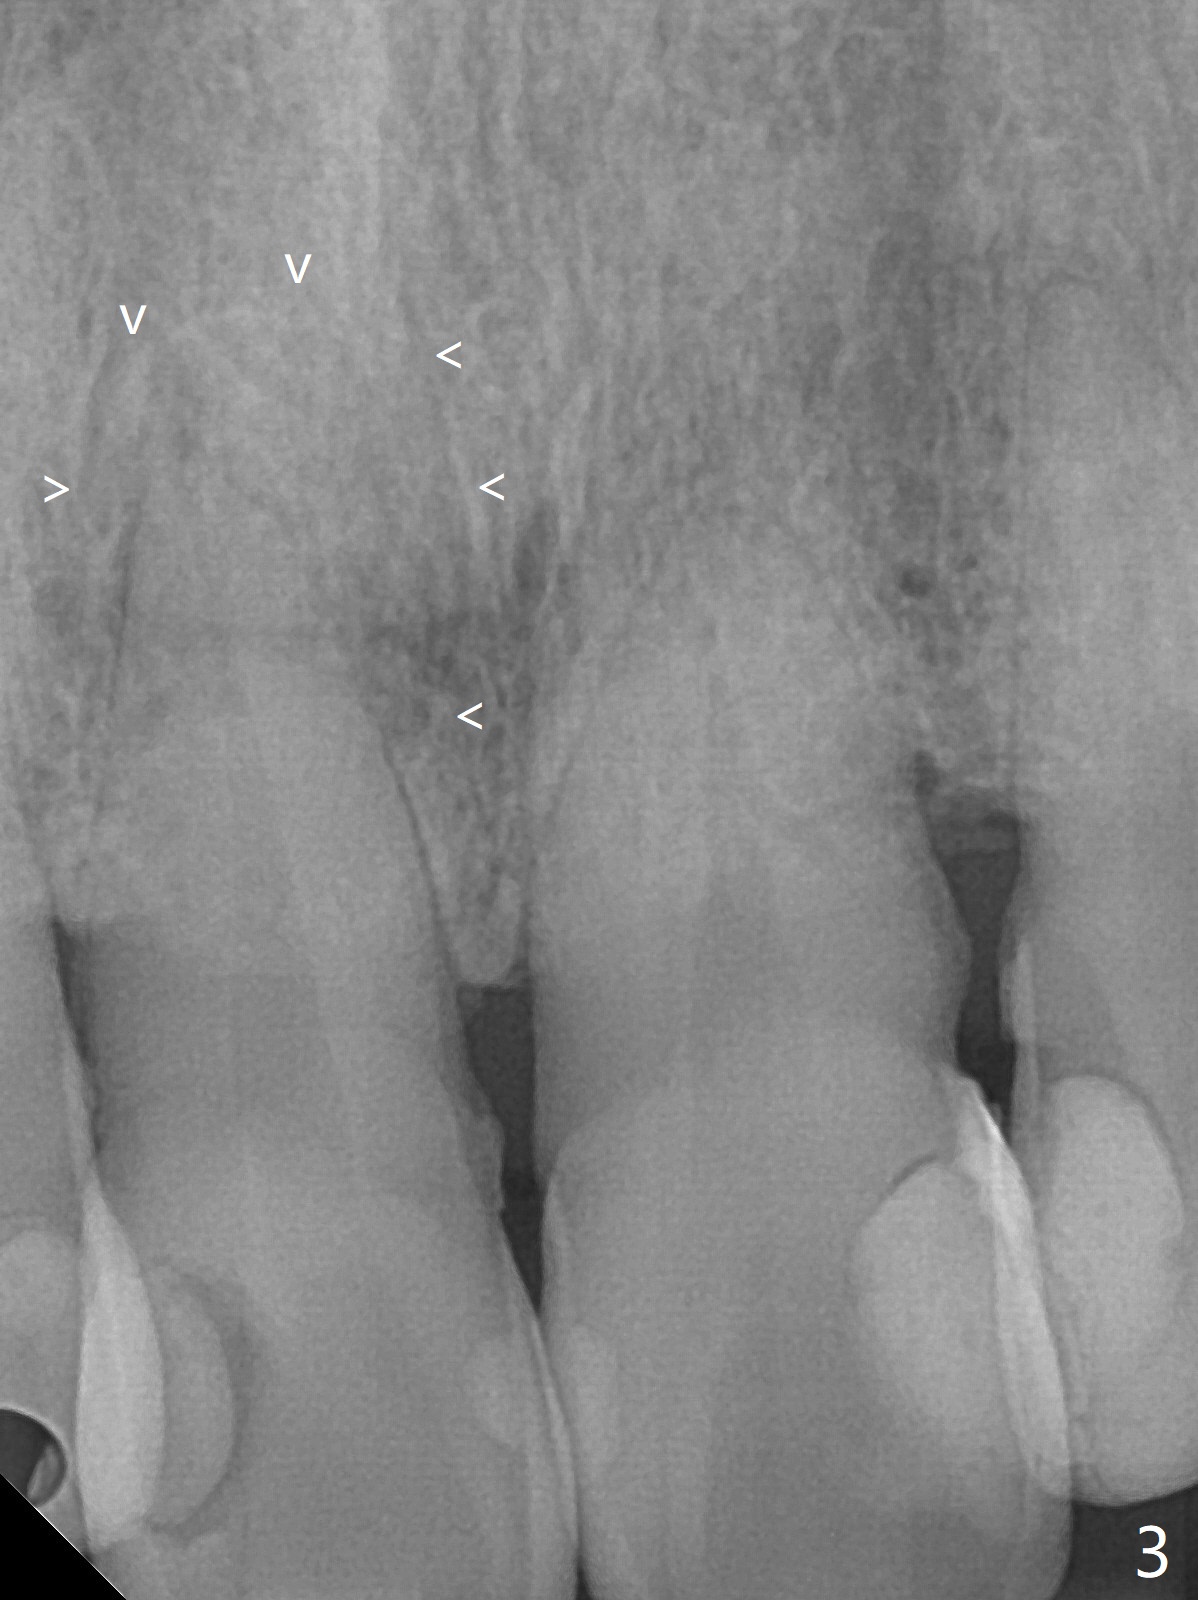

单个门牙变色往往是牙髓坏死所致,根管充填后做漂白,防止漂白泡沫跑到根尖孔之外,这种顺序可以改变吗?53岁女右上1根尖无痛性红肿(图一:^),牙冠变色(图二),牙髓测定:死髓,伴有根尖阴影(图三),中切牙需要根管治疗,什么时候漂白最好,步骤便利?根管治疗后做内漂白,必须把牙胶尖取出,釉牙骨质交界处之下,牙冠长,如这个病例,取出可能困难。我们准备尝试根管治疗当中做漂白,由于死髓牙,根管治疗可以不需要局麻,三个牙齿暴露在橡皮障之外(图四),以便术中漂白观察。根管治疗当中使用大量漂白水,好象并没有改善颜色(图五)。所以在根管口(图六)注入35%双氧水(漂白液,胶状),适当超越釉牙骨质交界处。万一双氧水气泡跑出根尖孔,我们将用生理盐水冲洗,不过这个意外没发生。双氧水也放置在患牙表面(外漂白),两次漂白后(每次20分钟),病人满意牙冠颜色改变(图七)。冲洗,擦干后,在根管中放置氢氧化钙糊剂。预约一个月后完成根管充填,如果牙冠颜色反弹,再次漂白。充填前需要多次冲洗,清除残余双氧水,后者抑制树脂固化。